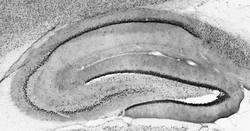

73-117 IHC

Full details

Method:

Other validation